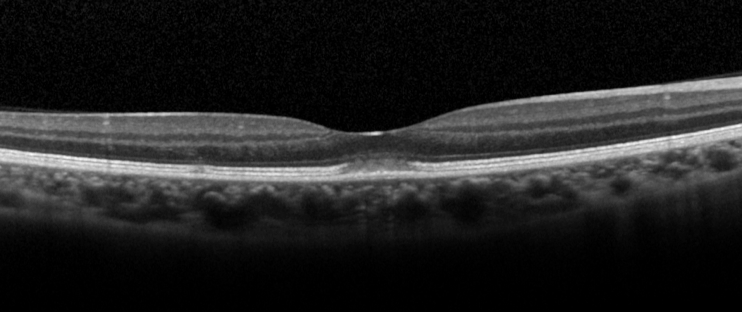

Optical coherence tomography

Optical coherence tomography (OCT) is the investigation of choice for diagnosis and follow-up of patients. The characteristic OCT feature is a dome-shaped hyperreflective lesion at the photoreceptor outer segment layer disrupting the ellipsoid zone and interdigitation zone (Figure 3).[1][5] The outer nuclear layer may be involved by the hyperreflective lesion.[2][5] In the early phase of the disease (within 2 days of symptoms onset), upward displacement of the external limiting membrane and mild transient thickening of the RPE/Bruch’s complex can be seen.[5]

During recovery, OCT shows a typical pattern where the inflammatory lesion reduces in height and the retinal layers restore in order from inner to outer layers (Figure 4). The recovery involves a sequence of: (1) decrease in height of OCT hyper-reflective lesion and the displaced external limiting membrane returned to its normal position with irregularity, (2) complete disappearance of the hyper-reflective lesion, (3) restoration of external limiting membrane, (4) restoration of ellipsoid zone, and (5) restoration of interdigitation zone (Figure 4).[5] Occasionally, there is a persistent defect in the OCT ellipsoid zone associated with incomplete visual recovery.[19]